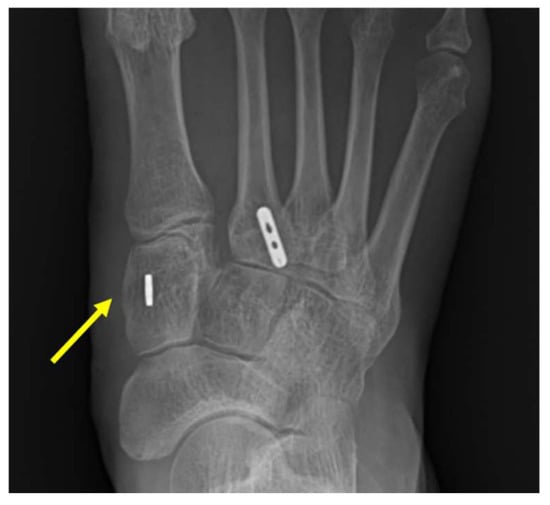

| Single TightRope Technique |

|

| Dual TightRope Technique |

| Internal brace Technique |